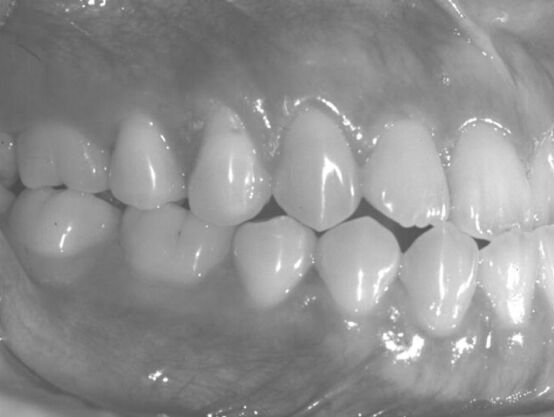

6.圖中所示之上顎咬合情況之名稱為何? (A) 頰側錯咬 (B) 完全頰側錯咬 (C) 舌側錯咬 (D) 完全舌側錯咬

7.圖中臼齒所示之關係為安格氏分類中的何種關係? (A) 正常咬合 (B) 第一級臼齒關係 (C) 第二級臼齒關係 (D) 第三級臼齒關係